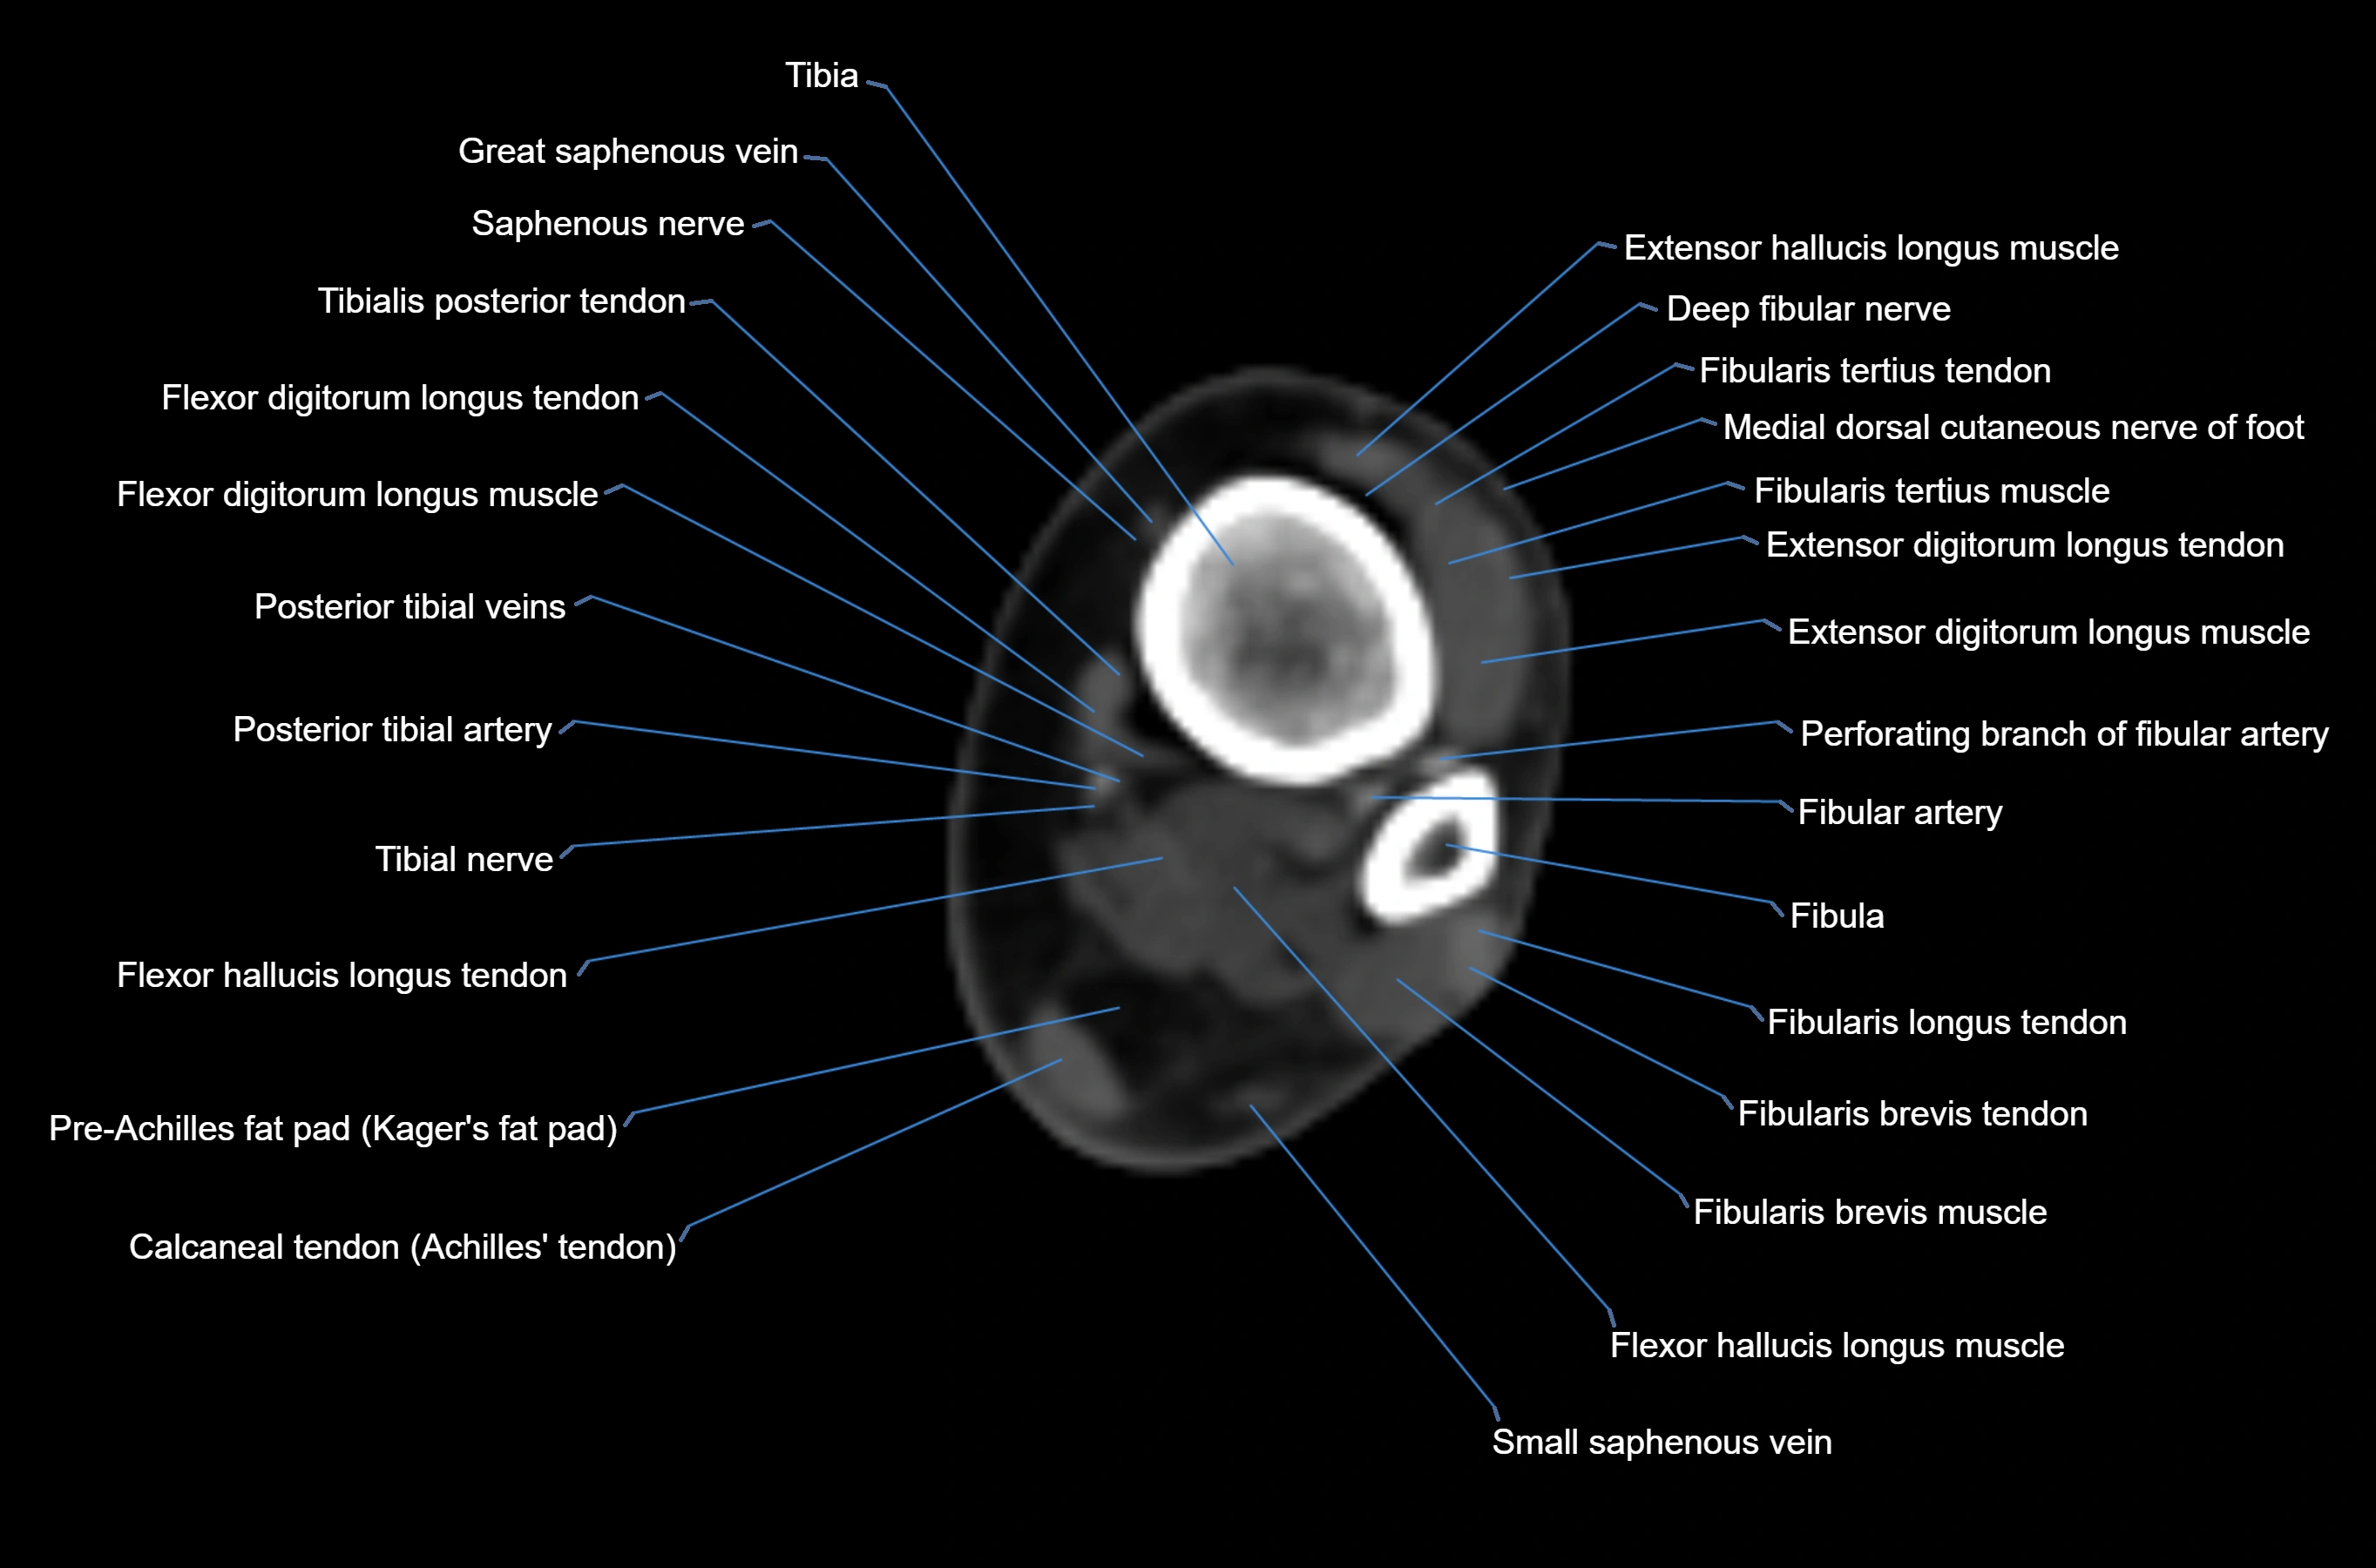

CT image